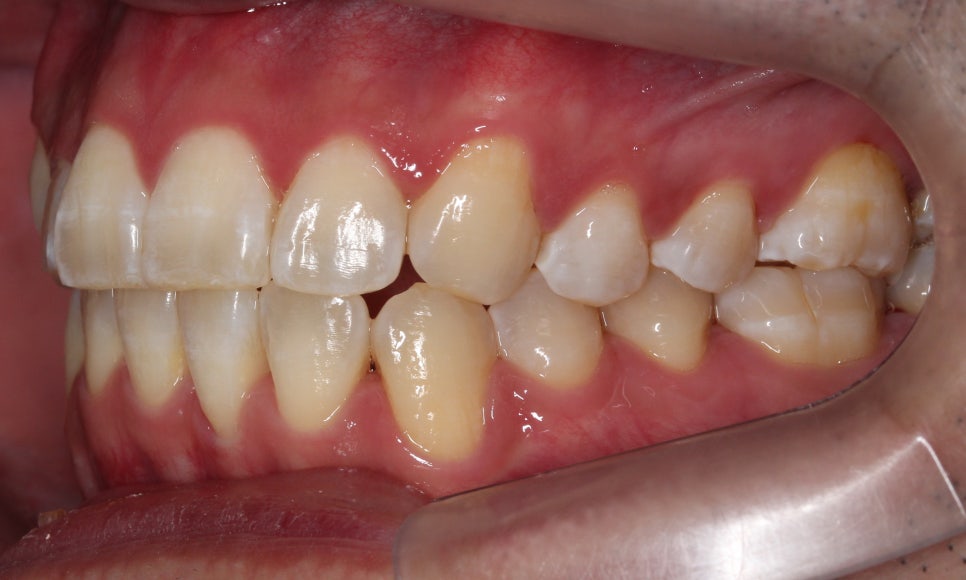

배열이 처음보다 훨씬 좋아졌습니다.

차이가 조금 더 느껴지실까요 ?^^

마찬가지로 좌 before, 우 after입니다.

이렇게 보면 훨씬 개선된 것이 눈에 띄시죠?^^

부분교정으로 진행하는 것이다 보니

전체 교정보다 완벽할 순 없지만,

환자분께서 매우 만족하셨습니다.

가장 신경 쓰여하셨던 #12 치아가

앞으로 나오면서 훨씬 가지런해지고

아래 치아 치축도 개선되면서

더욱 정돈된 이미지를 가지셔서

크게 만족하셨습니다.